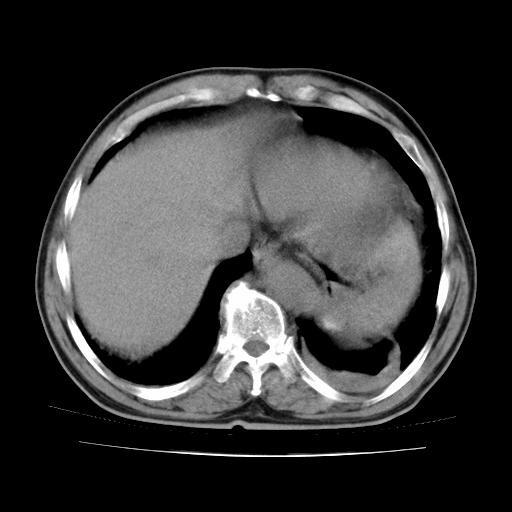

男,71岁,咳嗽,气喘10年,再发并咯血.胸片见气胸

考虑  左肺中心型肺癌伴阻塞性肺炎,肺不张,纵膈淋巴结肿大。慢支炎,肺气肿,左侧气胸肺压缩5%

左侧中央型肺癌伴纵膈淋巴结转移。

左肺中心型肺癌伴阻塞性肺炎,肺不张,纵膈淋巴结肿大

1)考虑左肺中心型肺癌伴阻塞性肺炎、左肺下叶肺不张、左侧肺气肿,纵膈淋巴结转移。2)左侧气胸(肺组织压缩约5%)。

左肺中心型肺癌伴阻塞性肺不张、肺气肿 。

1)考虑左肺中心型肺癌伴阻塞性肺炎、左肺下叶肺不张、左侧肺气肿,纵膈淋巴结转移。2)左侧气胸。